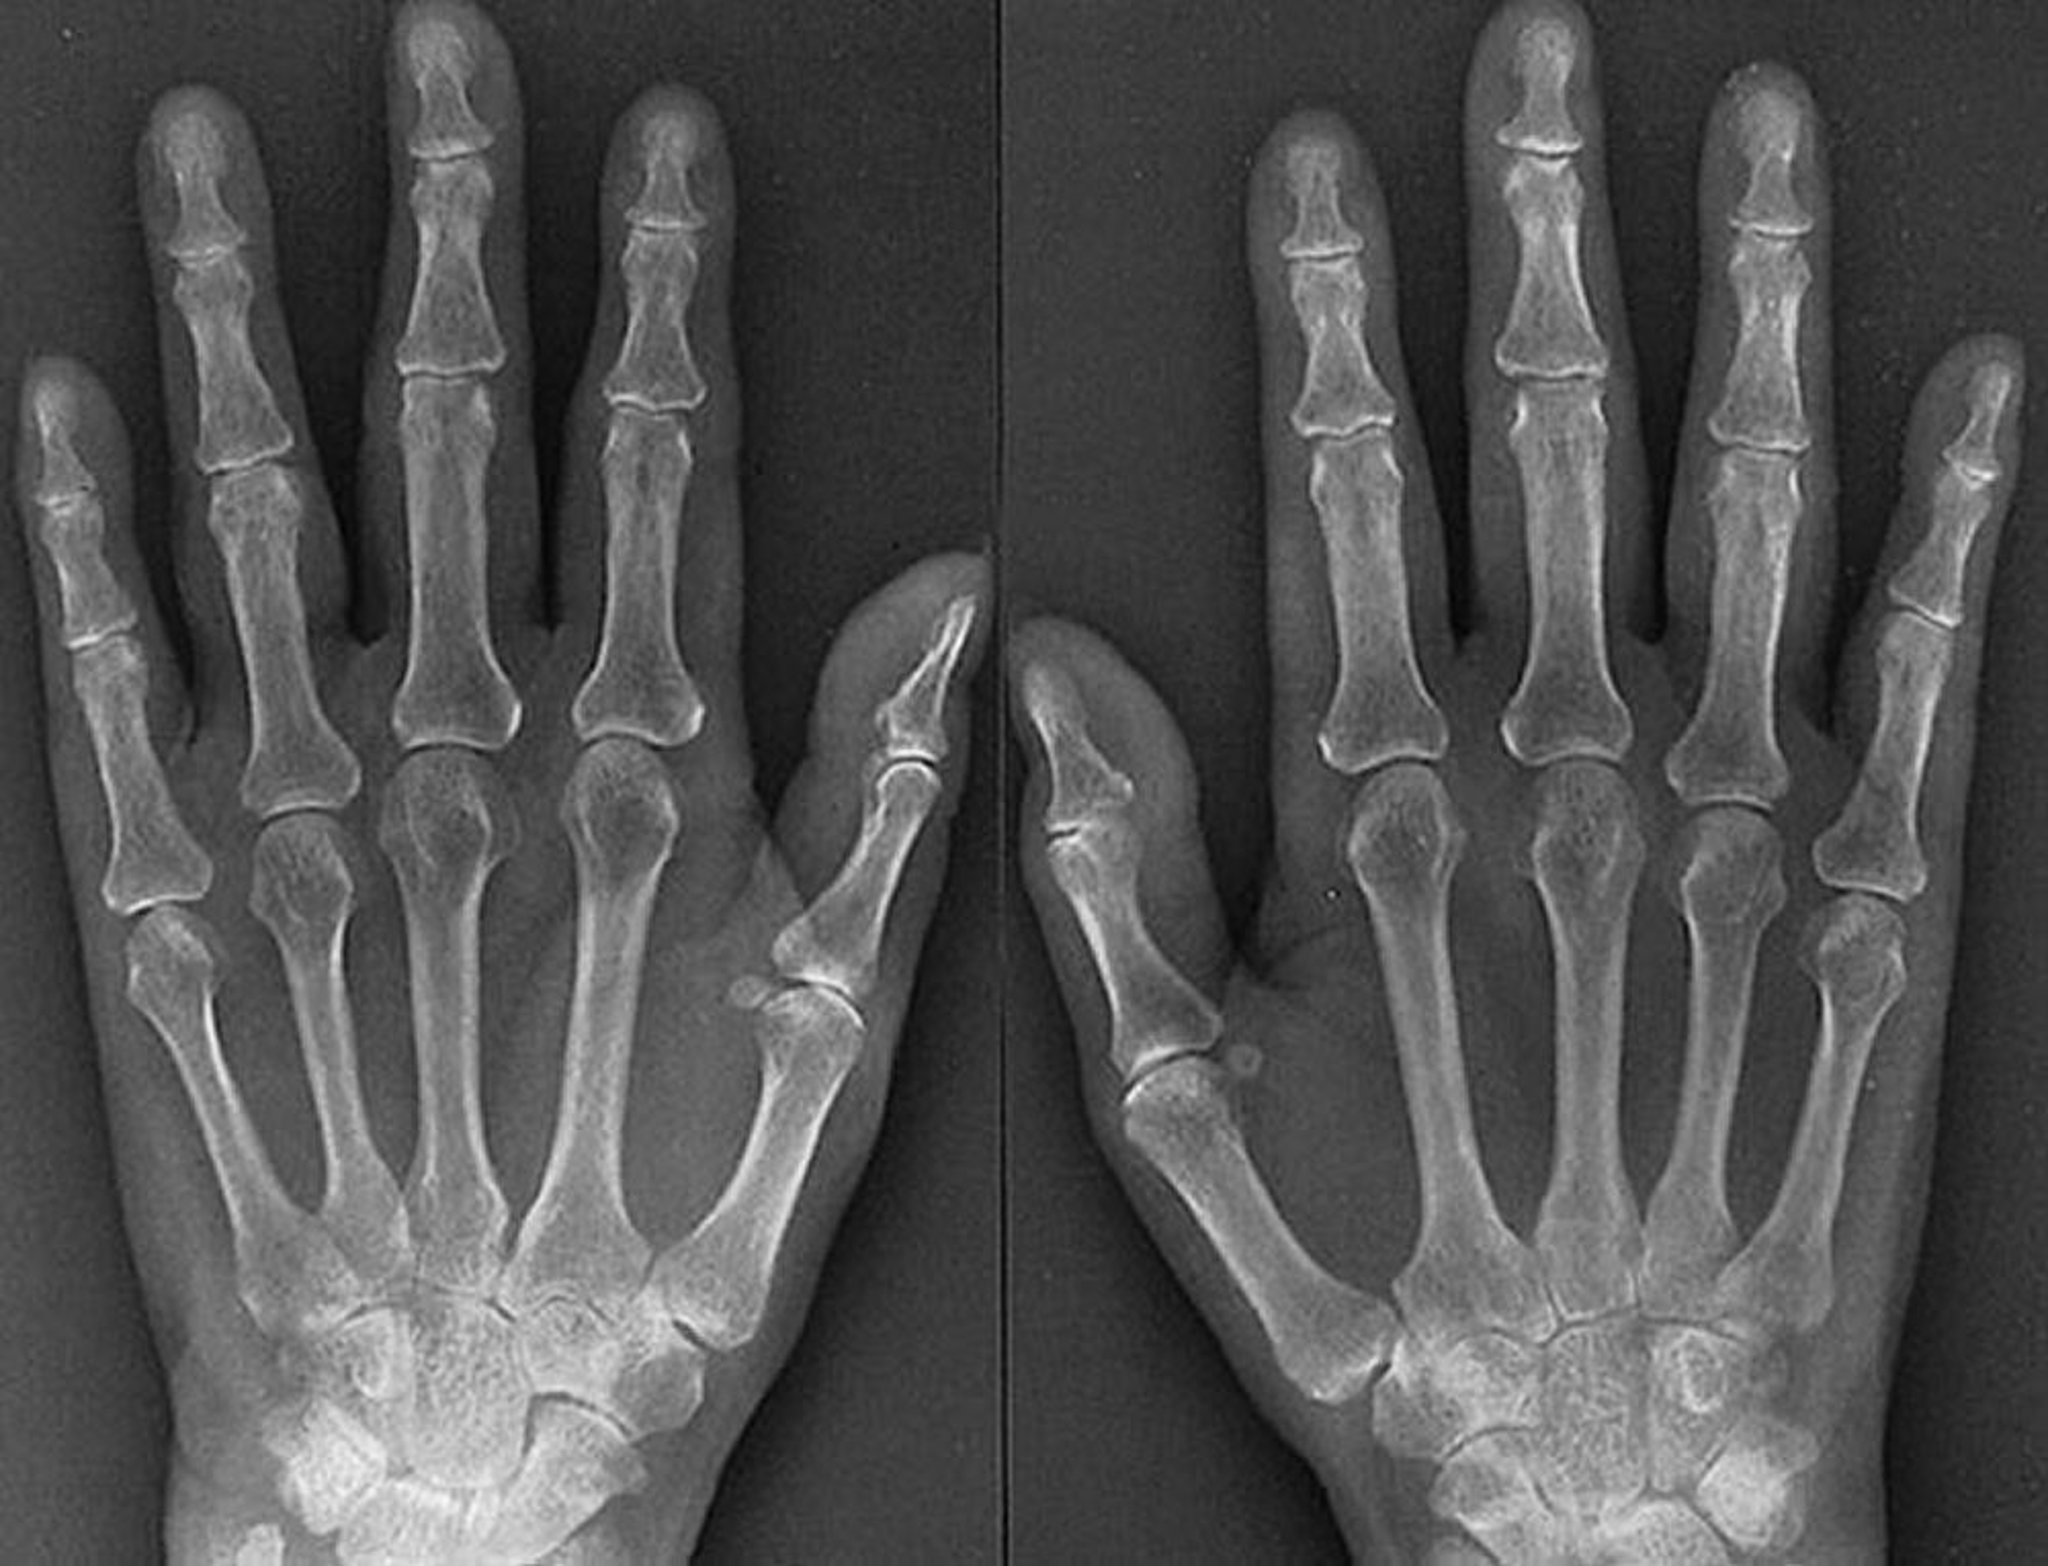

Đặc điểm X-quang của viêm khớp dạng thấp giai đoạn đầu

Các đặc điểm của bệnh viêm khớp dạng thấp giai đoạn đầu, tiến triển mạnh, như đã quan sát thấy trên phim chụp X-quang của một phụ nữ 61 tuổi bị viêm khớp dạng thấp trong 1 năm, bao gồm bằng chứng sưng mô mềm ở các khớp ngón tay và khớp gian đốt gần, loãng xương quanh khớp, hẹp khe khớp đối xứng của một số khớp bàn ngón tay và khớp gian đốt gần của cả hai bàn tay và các chỗ ăn mòn nhẹ của khớp bàn ngón tay thứ 3 bên phải và khớp bàn ngón tay thứ 4 bên phải và bên trái.

Được sự cho phép của nhà xuất bản. Từ Matteson E, Mason T: Atlas về Thấp khớp. Biên tập bởi G Hunder. Philadelphia, Current Medicine, 2005.